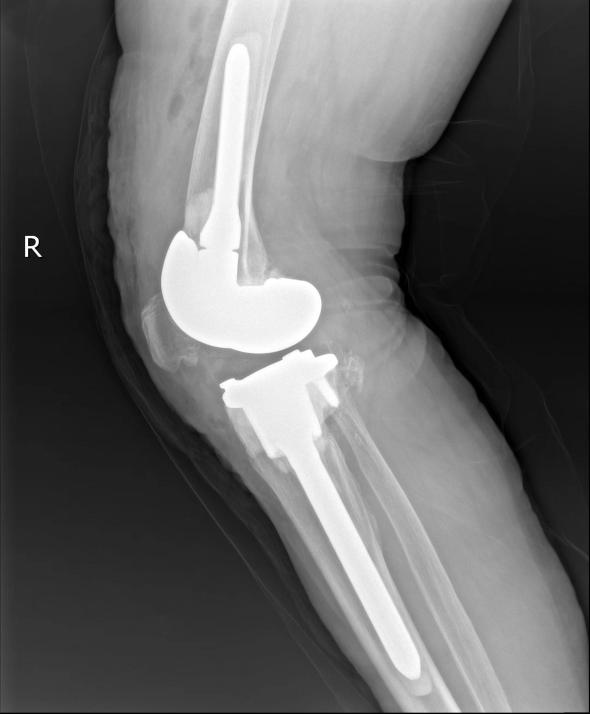

在充分做好个人防护的前提下,手术组医务人员分工协作、默契配合,整个手术过程有条不紊、十分顺利。手术完成后,李大娘被安全送返住院部单间隔离病房休养,术后X线检查发现,假体力线无偏差,髌骨轨迹良好,膝关节功能良好。李大娘和家人对治疗效果都非常满意。

12月13日,李杨教授、陈鹏副教授、彭启华医师身穿防护服、佩戴医用防护口罩、正压防护头罩、手套等防护用品,按照预定手术思路进行右侧膝关节翻修术。手术中,医务人员取出了磨损松动的胫骨、股骨侧假体和聚乙烯垫片,充分清除关节周围增生及坏死组织后,反复推敲,精心设计,将股骨和胫骨假体分别安装植入,再植入14mm聚乙烯垫片。